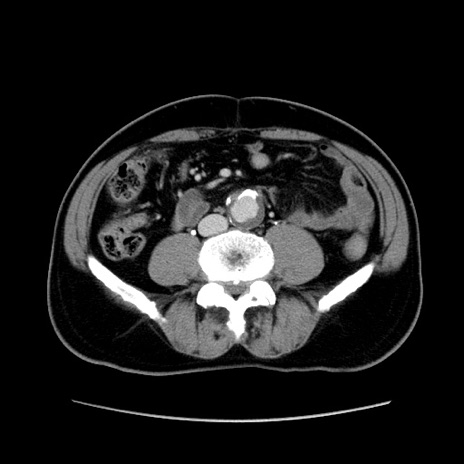

症例34(横断像)

【症例】60歳代 男性

【主訴】右鼠径部膨隆

【現病歴】1年程前より右鼠径部膨隆あり。自己にて還納可能だったため放置していた。3時間前より右鼠径部の脱出を認め、還納困難となり受診。

【既往歴】高血圧

【身体所見】右鼠径部に小児頭大の膨隆あり。弾性硬であり、用手還納は困難。左鼠径部にも膨隆を認める。脱出はなし。

【データ】WBC 15500、CRP 測定なし